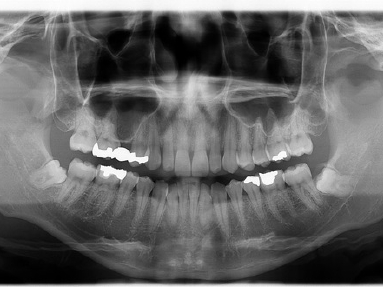

パノラマ写真(写真上)は一般的には全体像を見るのに適したレントゲンですが低解像度なために正確な診断のために追加撮影が必要でしたが、デジタル化によって高解像度化されているためそれだけで必要な情報を得ることができるようになりました。